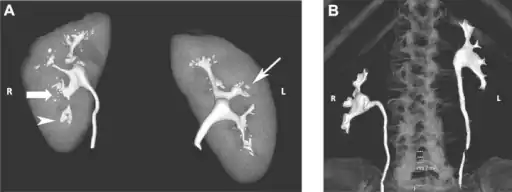

Frontal section through the kidney